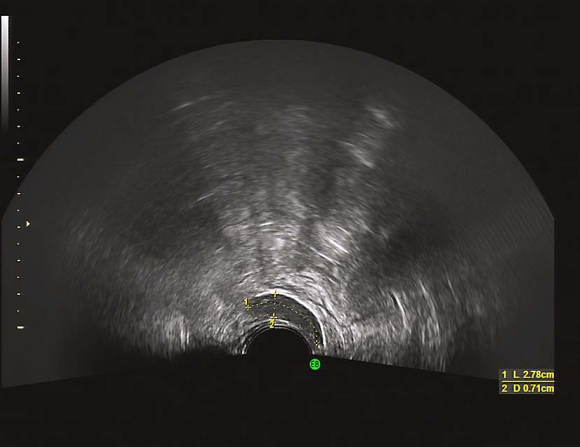

始基子宫二维超声